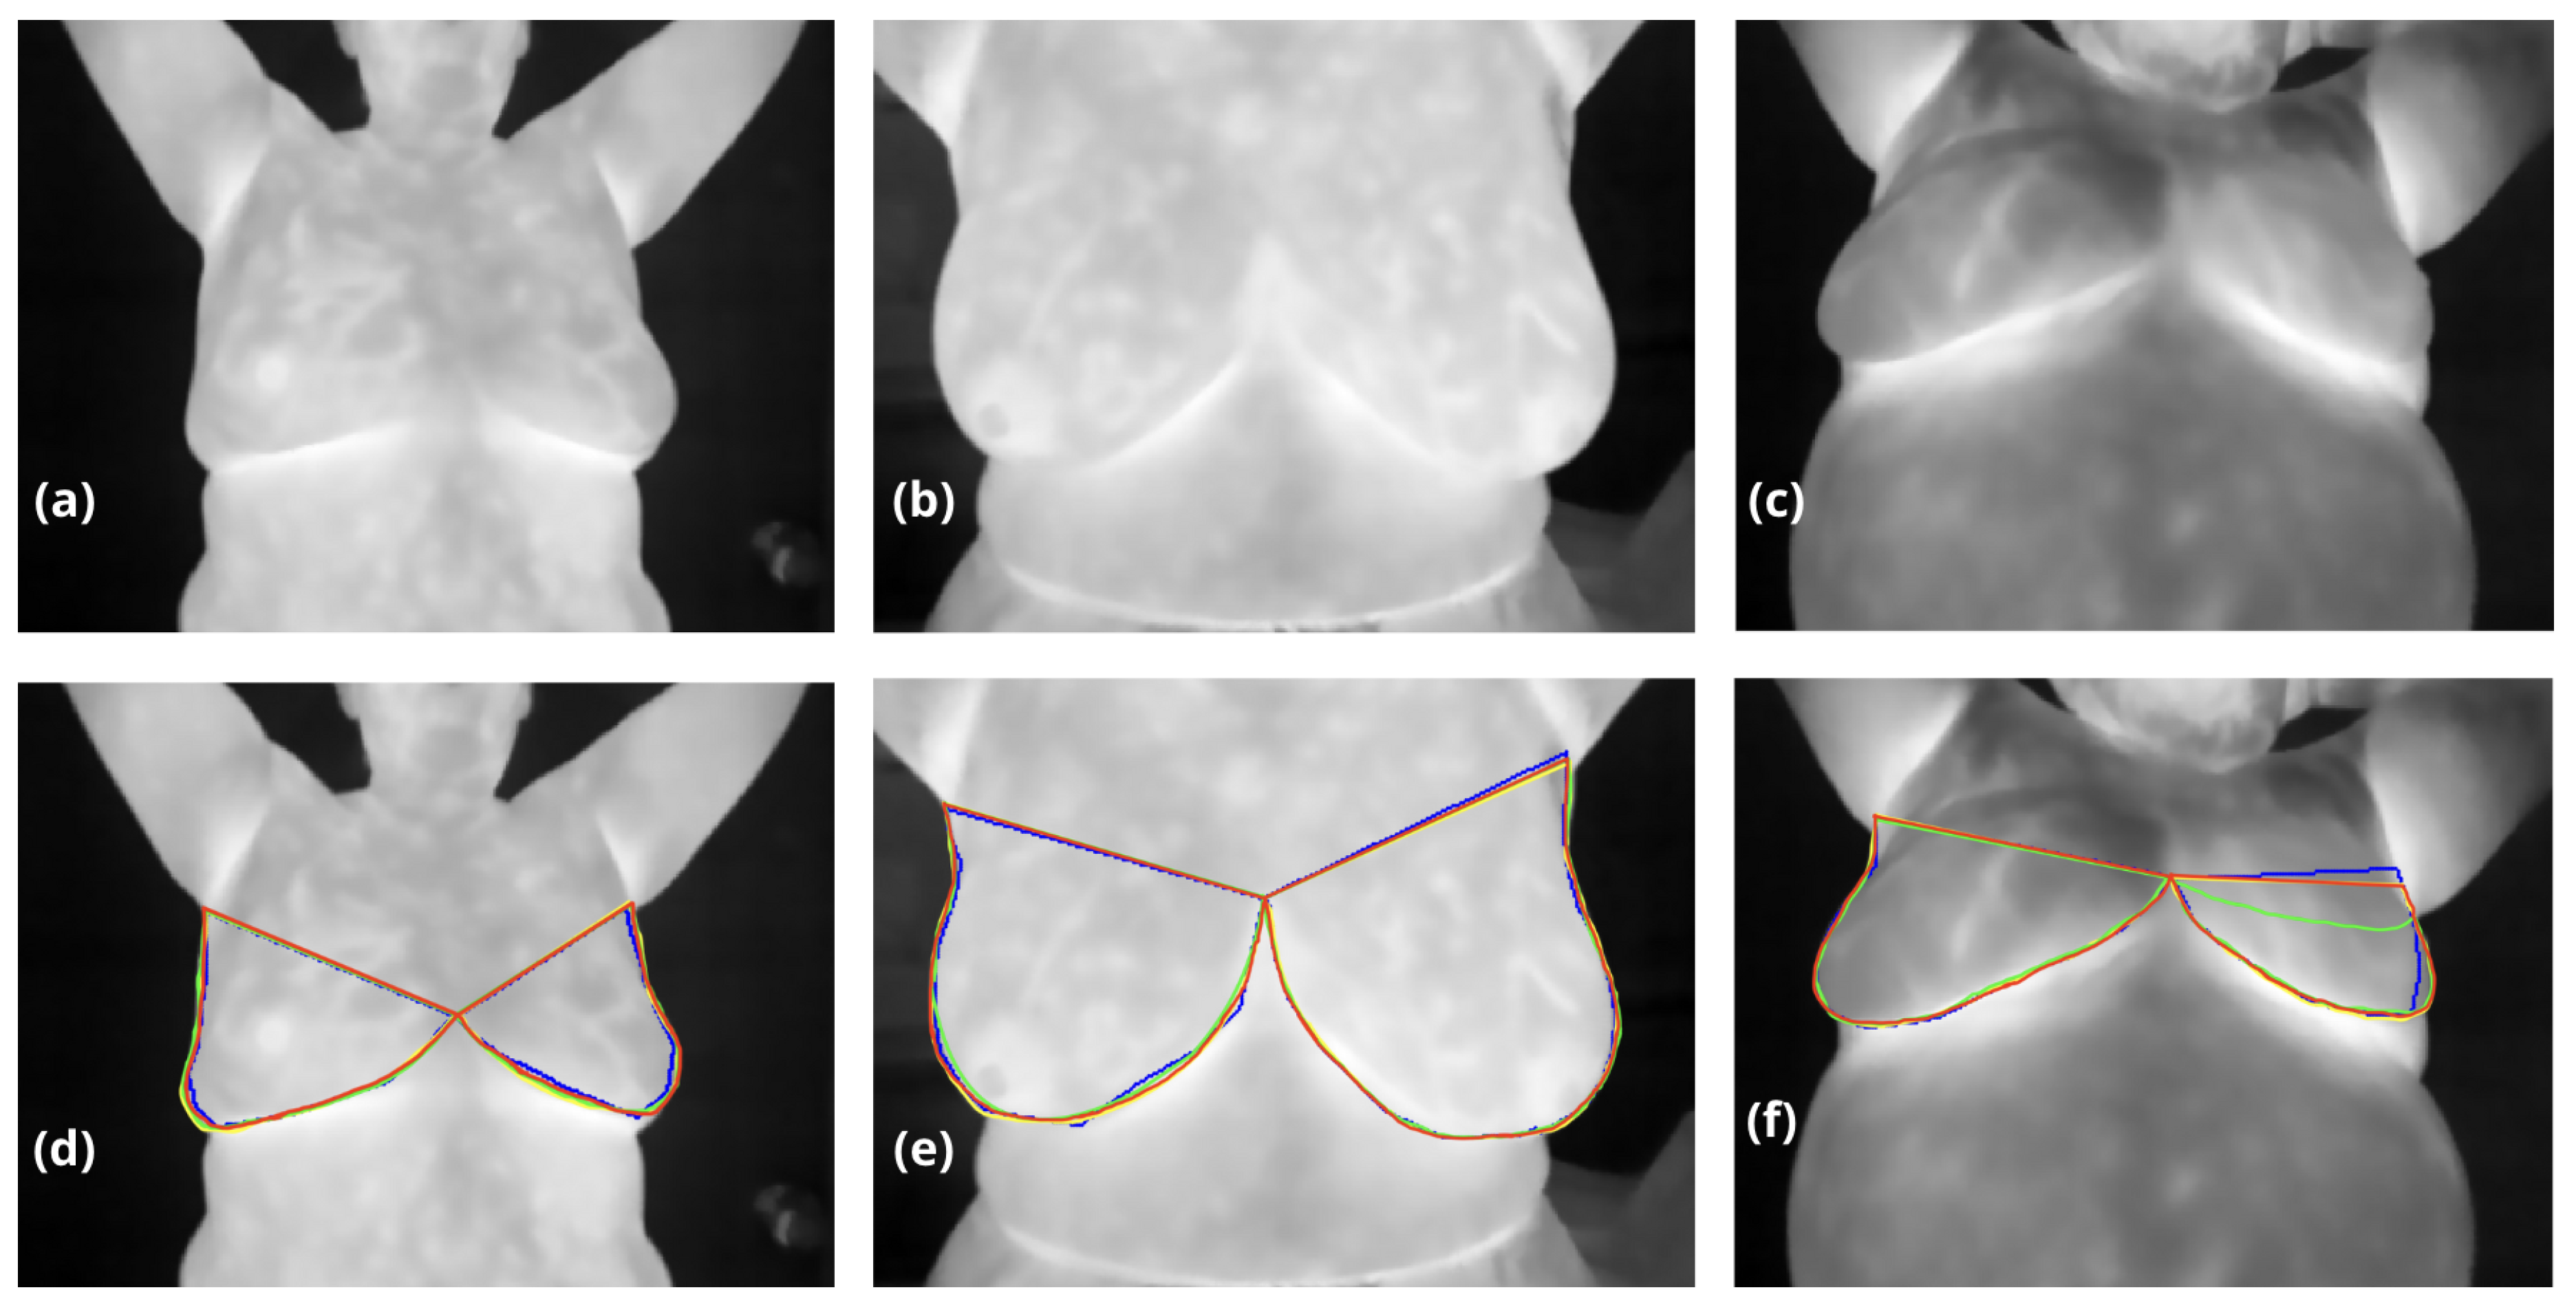

Table 1 compares the performance of traditional computer vision methods, a Dense Multiscale U-Net, and our proposed hybrid approach for breast segmentation, evaluated using the DSC and IoU. While neural networks demonstrate high reproducibility and achieve metrics comparable to traditional computer vision methods, their primary challenge lies in accurately defining the superior breast boundary, which in some cases appears eroded or poorly delineated, see Figure 5. This limitation is particularly evident in the Dense Multiscale U-Net results, where DSC and IoU scores reached 0.972 and 0.922, respectively, trailing slightly behind traditional methods. In contrast, our hybrid approach achieved the highest performance across both metrics, with a DSC of 0.987 and an IoU of 0.963, surpassing the computer vision method (DSC: 0.983, IoU: 0.934). This improvement underscores the effectiveness of combining traditional anatomical priors with the adaptability of neural networks, allowing for better boundary delineation and superior overall segmentation accuracy.

Figure 5. Testing thermographic images (a-c) are shown without noise to evaluate internal information. In contrast, segmentation results for breast regions are overlaid in images (d-f), with blue contours representing the Computer Vision method, green contours the Dense Multiscale U-Net, yellow contours our hybrid method, and red contours the ground truth masks validated by oncologists. Images (d) and (e) display relatively consistent results across the three approaches, despite low inframammary contrast in (d) caused by collapsed breast volume. In (f), the left breast’s upper boundary (visible on the right) highlights a clear underestimation by the Dense Multiscale U-Net, where thermal patterns were not accurately interpreted.